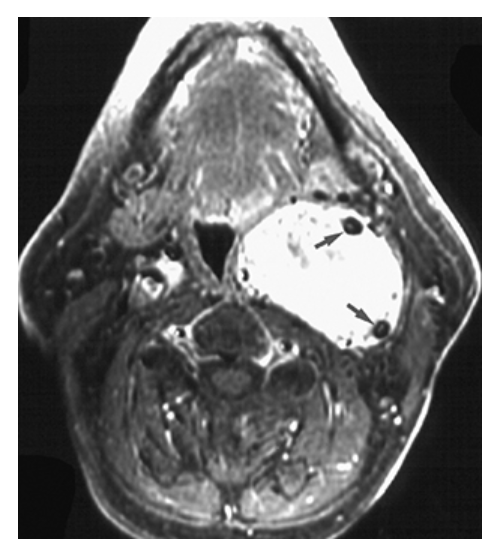

What does the figure show?

Parotid Gland Tumor. T1-weighted axial MRI of the parotid gland demonstrates a well-defined, round, low-signal intensity mass (arrow) in the posterior aspect of the superficial lobe of the left parotid gland.

Parotid Gland Mass. T2-weighted axial MRI of the parotid gland demonstrates a well-defined high-signal intensity mass (arrow) of the posterior aspect of the superficial lobe of the left parotid gland consistent with a pleomorphic adenoma.